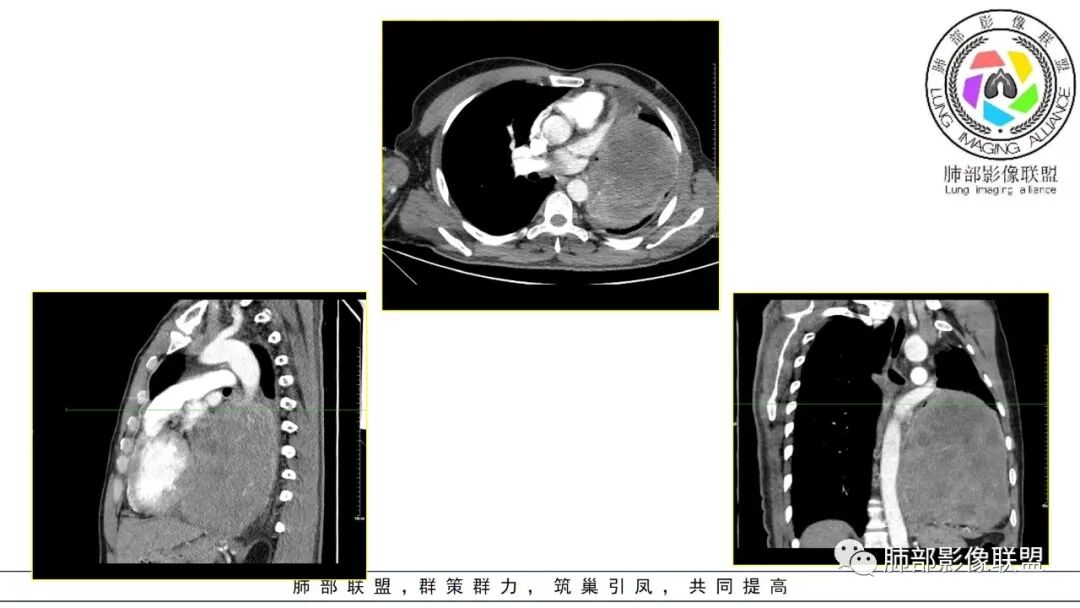

好发于肺胸壁交界区或纵隔交界区,病灶部位对病灶性质判断有较大价值。多单发,有包膜,边界清。

强化方式:多均匀或不均匀明显强化,增强肿瘤内可见迂曲血管影(蛇纹血管等),肿瘤较大可见“地图样”强化。

2.左肺巨大块影,上部边界较清楚,占据胸腔大部,对于左肺,“占据”及“推移”兼而有之,左肺上叶支气管推移狭窄,下叶支气管截断。下肺动脉穿行!

3.病灶密度不均,轻度强化,坏死或液化范围甚大,边界可分辨,部分“壁”可见钙化。